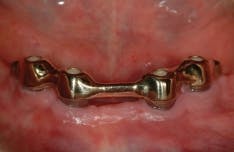

All-on-4 advocates claim that this type of treatment plan reduces cost and saves treatment time, but with the introduction of the ScrewIndirect one-piece implant that provides the implant, abutment, comfort cap, and transfer at a fraction of the cost of the implant alone from all the major implant companies, the economics argument for using the minimum number of implants is no longer valid. The ScrewIndirect screw-receiving platform allows splinting of implants that have up to 40 degree divergence, allowing distal angulations of up to 20 degrees if desired. Placement of five implants in the lower symphysis and six anterior to the maxillary sinuses can be relatively straight and still support adequate length of distal cantilevers. Four ScrewIndirect implants can also be placed, as shown below, splinted with a distal attachment for retention of an overdenture, but providing the patient with a fixed-detachable prosthesis that eliminates the need for a removable prosthesis is a more natural solution to restoring an edentulous jaw.

The ScrewIndirect one-piece implant offers a 3.0 mm D implant with adequate strength. All four diameter options (3.0 mm, 3.7 mm, 4.7 mm and 5.7 mm) have the same 5 mm D multi-unit platform. The 3.0 mm D implant allows treatment of narrow ridges and simplifies accurate placement during flapless surgery. Providing teeth in one day to edentulous patients and immediate implant placement following extractions is becoming the treatment of choice. The patient's existing denture is converted to a fixed-detachable prosthesis immediately following implant placement. This is accomplished by attaching titanium sleeves to the implants that project through holes cut in the denture and attached them to the denture with cold-cure acrylic followed by shortening the denture flanges.